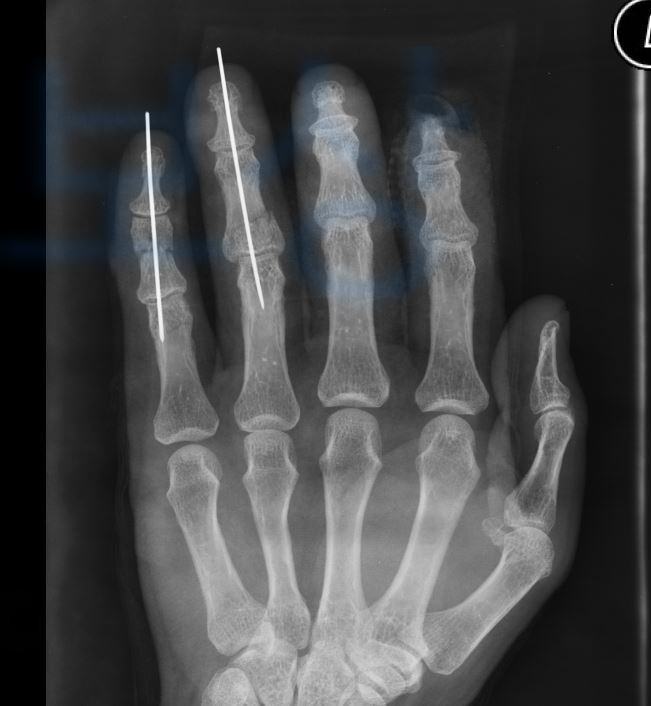

위 사고로 인해 안타깝게도 검지부터 새끼손가락까지 치료를 받으셔야 했는데

위 사고로 2수지는 경지골 절단, 4수지 5수지는 금속 고정술을 하셔야 했죠. 먼저 손가락의 장해등급 약관은 이러합니다. 그런데 중요한 것은

4수지 5수지의 기능장해 인정되어 산재 장해등급 11급 9호 받았습니다!

그 결과 AMA 방식의 장해 평가로도 4수지 5수지의 뚜렷한 장해에 해당되었습니다. 물론 장해진단서뿐만 아니라 이후 보험사의 심사에 대응하는 과정이 필요하지만 결국 저희가 처음 청구한 지급률 10% 모두 인정되어!